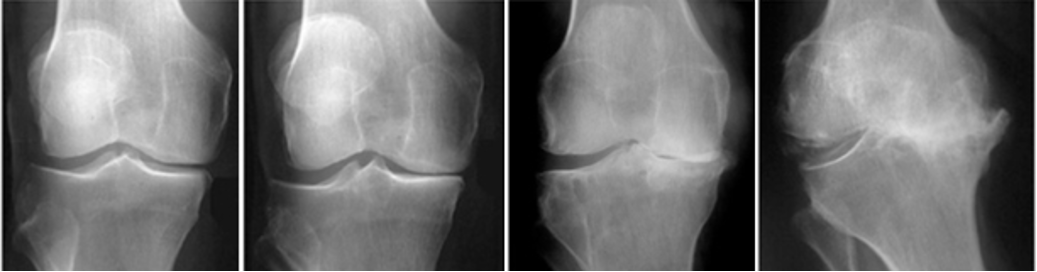

Cisto de Baker e artrose do joelho

Existe uma relação forte entre cisto de Baker e artrose do joelho. Em pessoas com osteoartrite, o aumento da produção de líquido sinovial, a inflamação e o derrame articular favorecem a formação e manutenção do cisto. Estudos mostram que o cisto pode aumentar a carga de sintomas nesses pacientes.

Por isso, quando o paciente apresenta cisto de Baker e artrose, o tratamento deve enxergar o joelho como um todo, e não apenas a bolsa de líquido atrás da articulação.